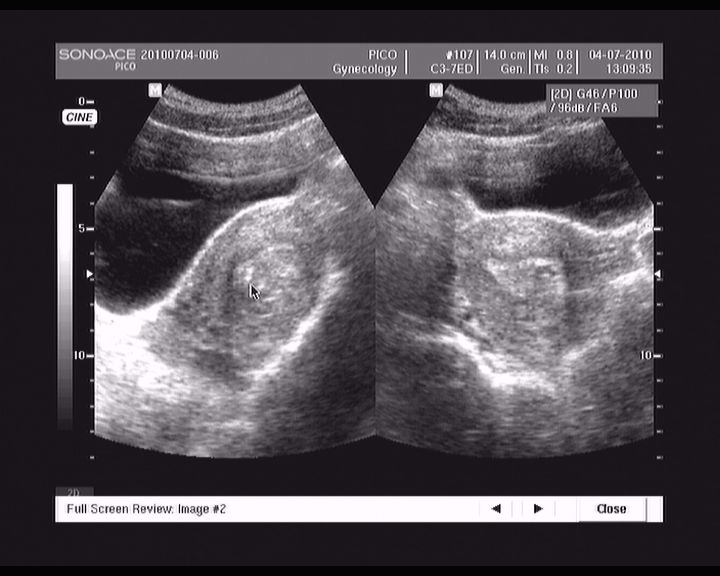

abrasio 01.07.2010

113.jpg